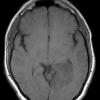

NEOPLASMS (GLIAL)

Astrocytoma, IDH-mutant, WHO Grade 2 (2)